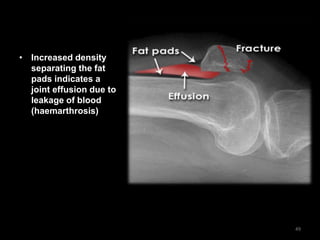

Patellar fracture - Lateral

• Increased density

separating the fat

pads indicates a

joint effusion due to

leakage of blood

(haemarthrosis)